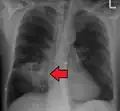

Pulmonary abscess on CXR

Lung abscesses are often on one side and single involving posterior segments of the upper lobes and the apical segments of the lower lobes as these areas are gravity dependent when lying down. Presence of air-fluid levels implies rupture into the bronchial tree or rarely growth of gas forming organism.